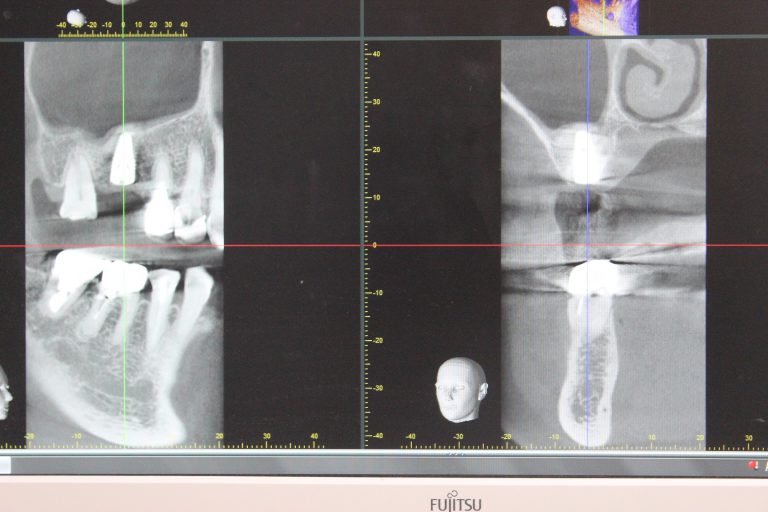

こちらが約半年前のCT写真。

白い部分(骨)がほとんどなくてインプラントができる状態ではありませんでした。

手術です。こちらがそのCT写真。

骨がドーム状に盛り上がり、密に詰まっています。